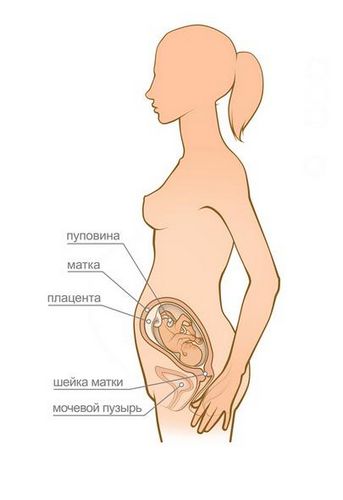

Збільшення ваги на 24 тижні становить 5,5-6 кг. Матка досягає рівня пупка, і животик майбутньої мами стає помітний оточуючим. У цей період на шкірі живота можуть з'явитися розтяжки і пігментні плями. Пупок поступово згладжується і виступає вперед. Після народження дитини пупок повернеться до свого звичного стану.

Кров'яний тиск вимірюється по черзі на двох руках у положенні сидячи. Отримані цифри порівнюються з тими, що були отримані при першій явці. Підвищення систолічного тиску на 25 мм рт.ст. і діастолічного на 15 мм рт.ст. від вихідного свідчить про розвиток артеріальної гіпертензії і почався гестозе.Висота дна матки (ВДМ)

ВДМ вимірюється сантиметровою стрічкою в положенні лежачи на спині. За висоту дна матки приймається відстань від лона до найвищої точки живота. У нормі цей показник повинен відповідати терміну вагітності. На 24 тижні ВДМ дорівнює 24 см.

Окружність живота (ОЖ)

Для визначення ОЖ лікар охоплює сантиметровою стрічкою живіт жінки в найвищій точці і отримує потрібну цифру. Строгих норм тут не існує. Важливо, щоб ОЖ збільшувалася при кожному відвідуванні гінеколога.

серцебиття плоду

Сердечко малюка прослуховується в області пупка акушерським стетоскопом. На 24 тижні вагітності серце повинно добре вислуховуватися через черевну стінку. ЧСС плода в нормі становить 120-160 ударів в хвилину.